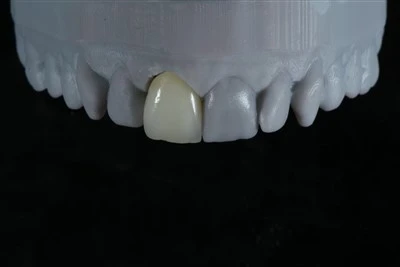

Prótesis parcial de acrílico removibleTiempo de respuesta: 3 días en laboratorio. Garantía: 5 años. Forma de envío: UPS (preferido), Fedex y DHL Linex. Armex también están disponibles. Pago:T/T, HSBC, PayPal, MoneyGram, Western Union